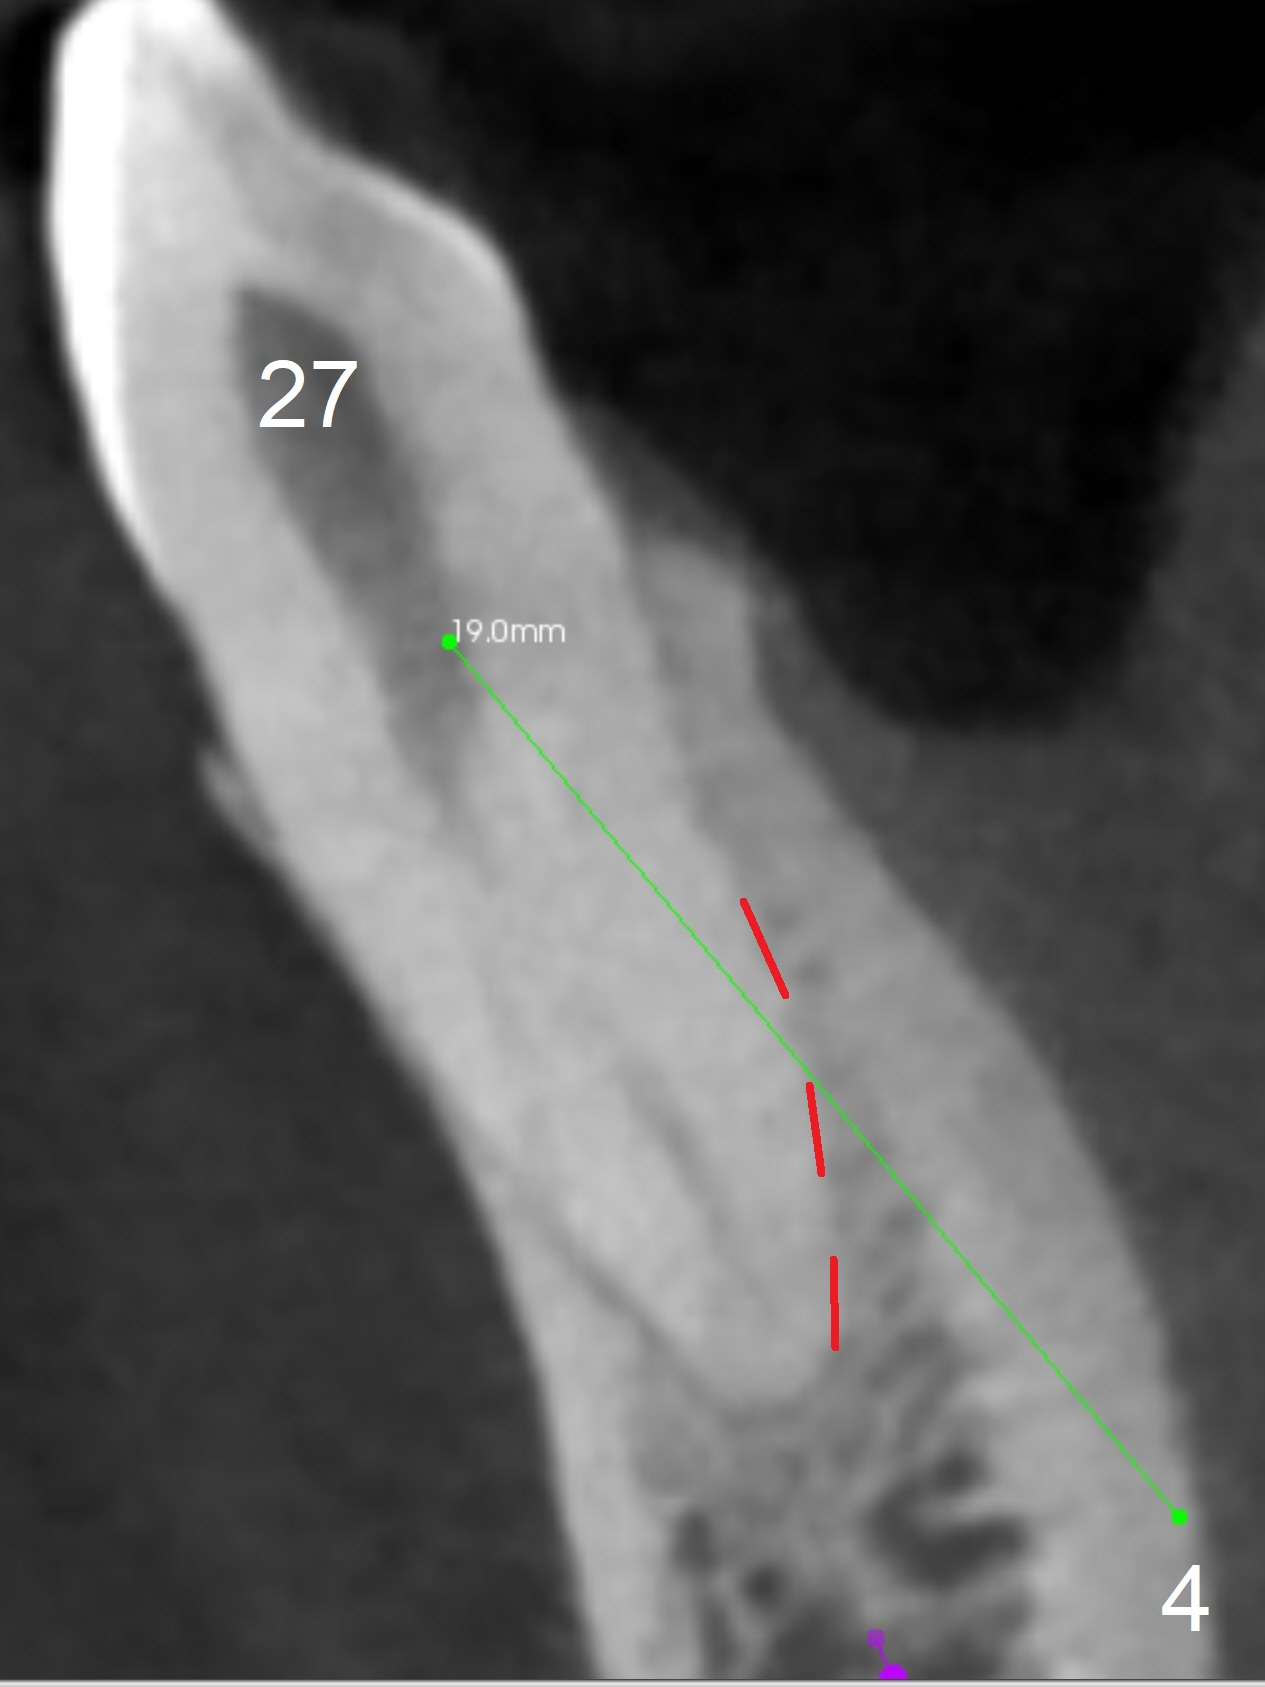

When the patient returns for #26 extraction and immediate implant and #27 RCT, it appears that the tooth #27 with subgingival margin distolingually is non-salvageable (Fig.1). She has dry mouth. Osteotomy is initiated in the lingual slope (Fig.4 red dashed line) of each socket with 1.2 and 2 mm drills for 16 and 19 mm at #26 and 27, respectively (Fig.2,3). The depth at #27 is subsequently reduced, while a 3x14(2) mm dummy implant is placed at #26 (Fig.5,6). A 3.8x13 mm implant is placed at #27 smoothly, while insertion of a 3x16(4) mm definitive implant (by mistake) has resistance (Fig.7). When the depth at #26 increases, there is feeling of perforation. The apex of the implant is truncated prior to reinsertion (Fig.8 >).

In fact the apex of the lateral incisor is also in the center of the alveolus (Fig.9 *). Osteotomy established in the lingual slope for a long distance (Fig.10,11) will perforate the lingual plate. The correct method of osteotomy is to set up in the middle of the socket and along the long axis of the alveolus with 2 fingers holding the alveolus (Fig.12 (2 circles)). The problem for this case is to use the lower RPD as a guide. With the RPD in place, the tactile sensation is lost.